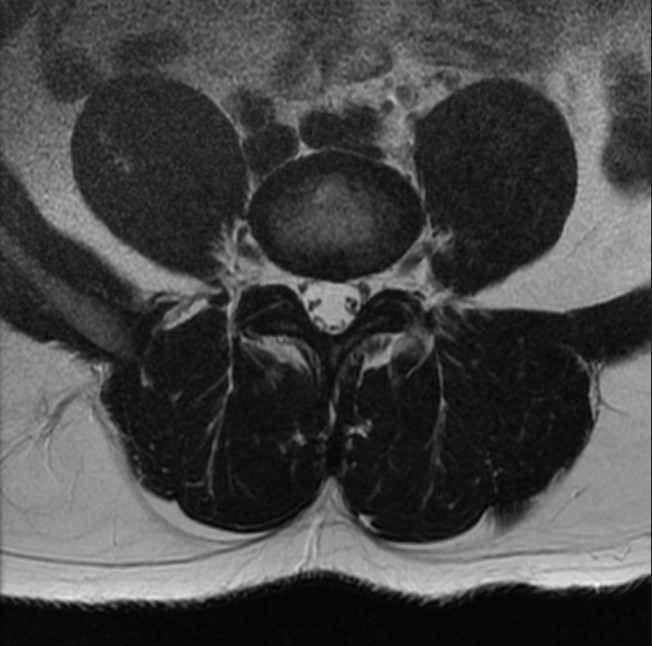

Normal Images Cervical Spine Lateral Xray Cervical Spine CT Cervical Spine MRI Sagittal Cervical Spine MRI Axial Lumbar Spine AP Xray Lumbar Spine Lateral Xray Lumbar Spine CT sagittal Lumbar Spine MRI sagittal Lumbar Spine MRI axial